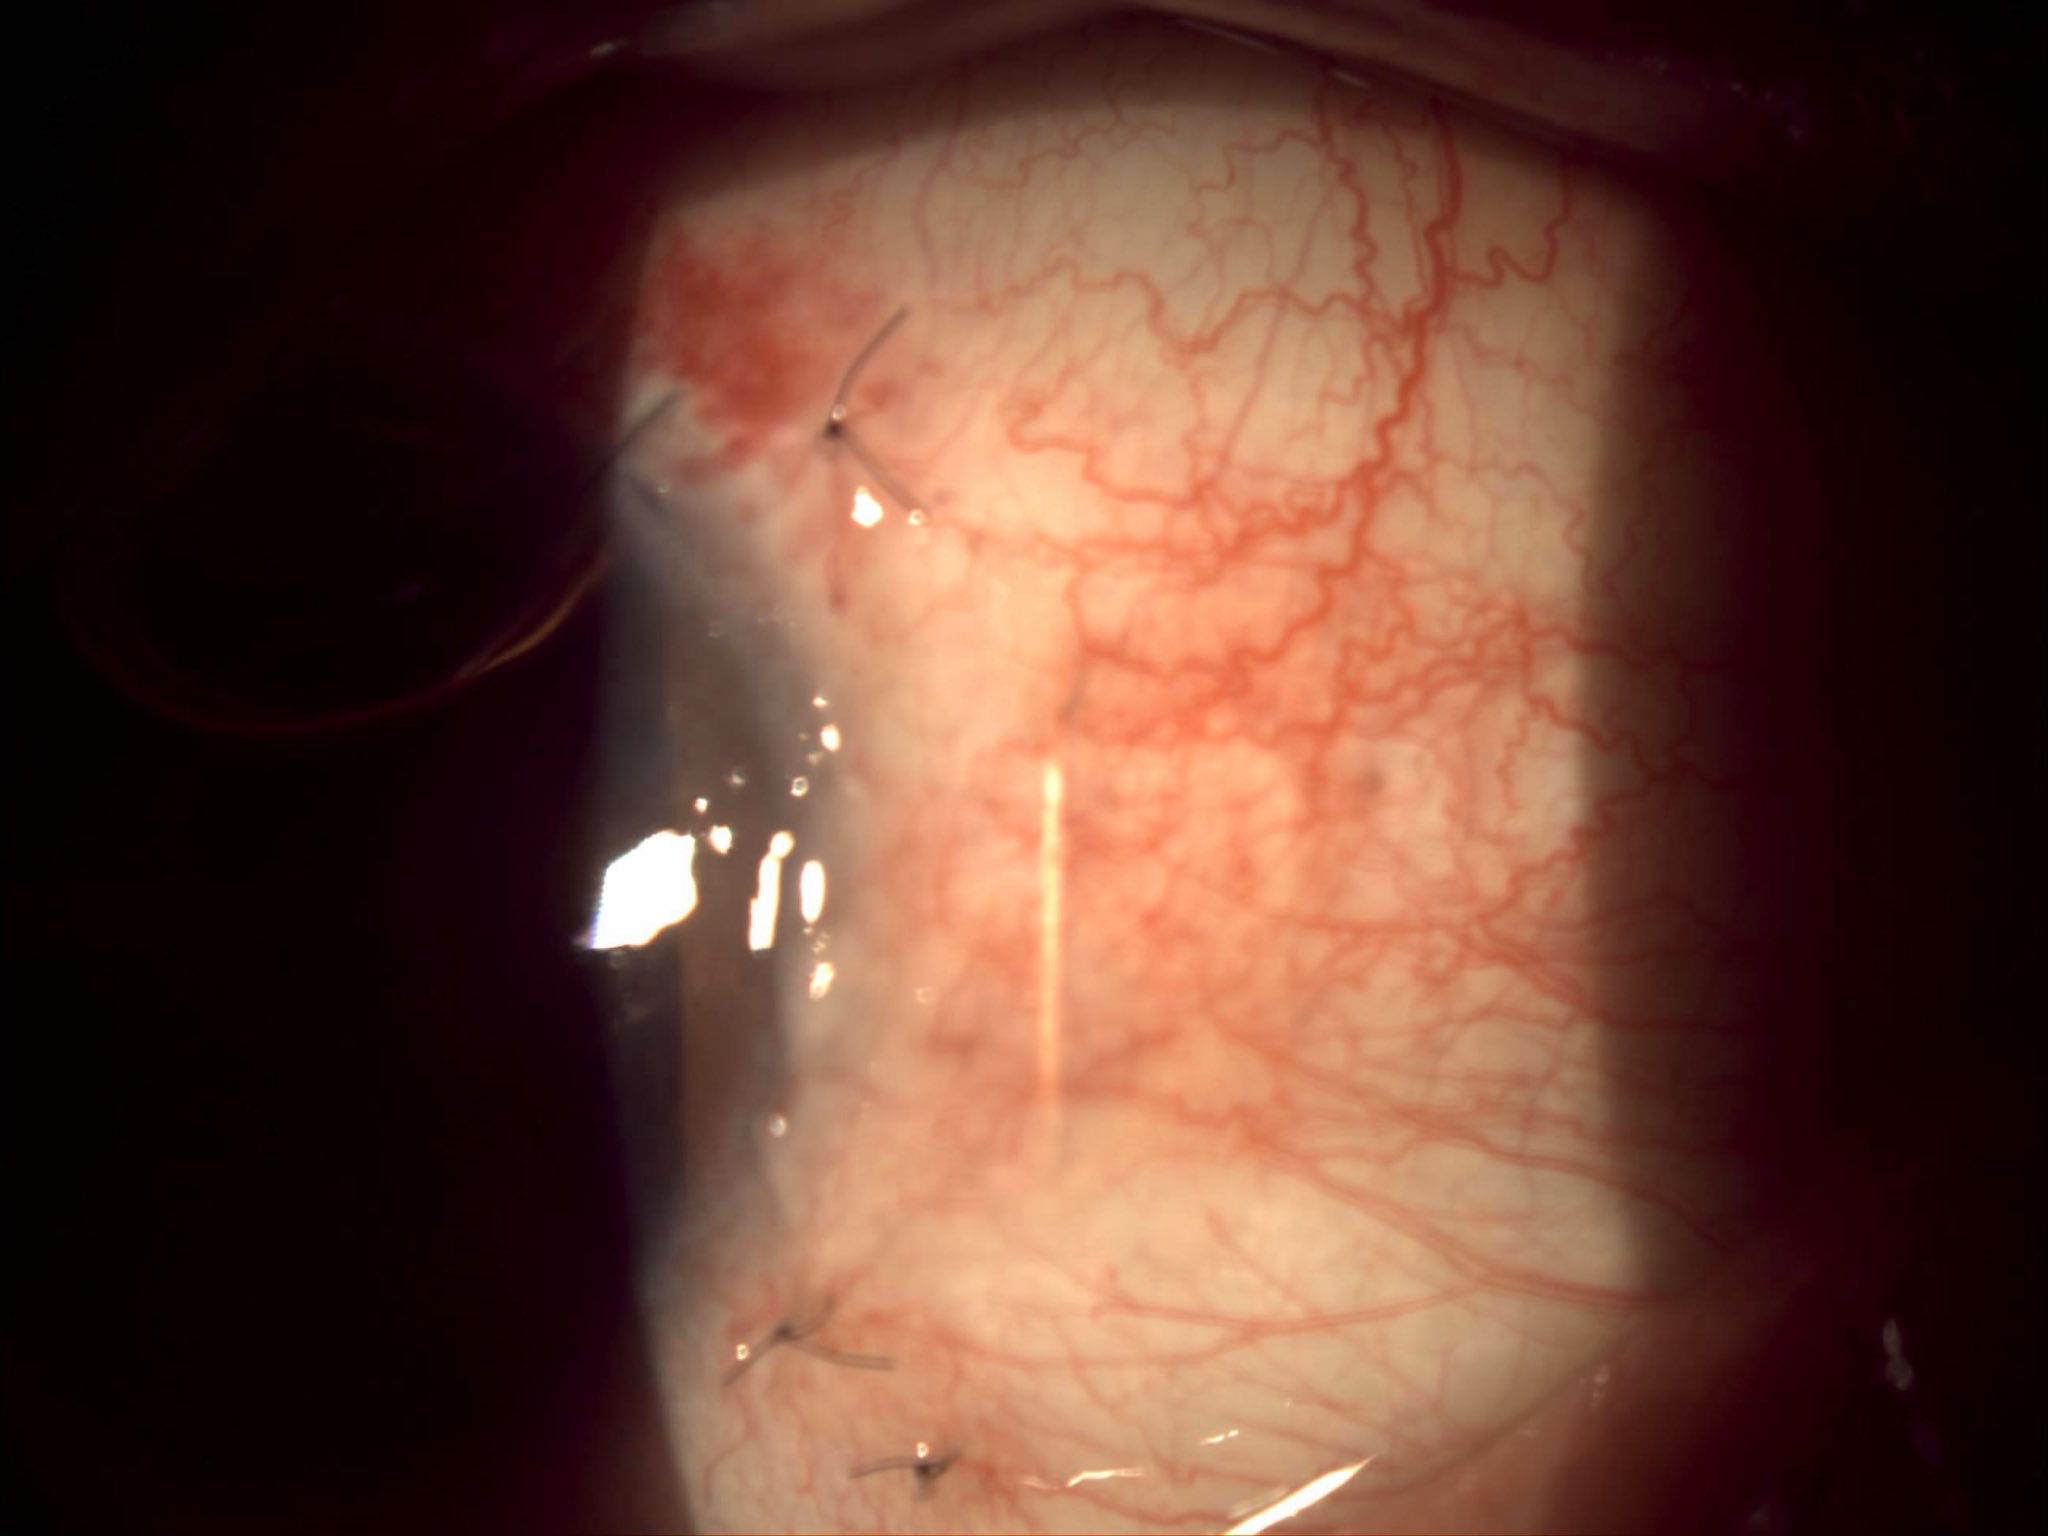

Cazul prezentat aici, deși pentru dr. Ozana Moraru nu a fost unul foarte deosebit, a fost, în schimb, pentru tinerii colegi, specialiști sau rezidenți, care au asistat la operație și, cu siguranță, a fost și pentru pacientă, victimă a violenței domestice, complet nevăzătoare din cauza traumatismelor repetate în zona feței și a ochilor, care au dus la cataractă hipermatură cu subluxație dein cristal la ambii ochi, unul fiind definitiv pierdut, prin glaucom secundar absolut. Legat de tinerii medici observatori, au avut ocazia să vadă o tehnică chirurgicală mai rar efectuată în zilele noastre, fiind mai veche, dar mereu actuală în aceste situații: tehnica intra-capsulară, prin care cristalinul opac și deplasat este extras “în bloc”, pe o incizie de 7-8 mm, care necesită a fi “cusută”, iar cristalinul artificial este unul special, adaptat lipsei de suport, trebuind prins prin diverse tehnici, fie la peretele ocular, fie la iris.

Fotografiile ochiului de azi, din prima zi postoperator (ultimele patru foto), arătau excelent, cu corneea fără pic de edem și cristalinul artificial perfect centrat și, mai mult decît atât, după consultație, stând în sala de așteptare fără pansament, pacienta se uita la televizorul din sală și comenta cu fiica ei ceea ce vedea acolo!